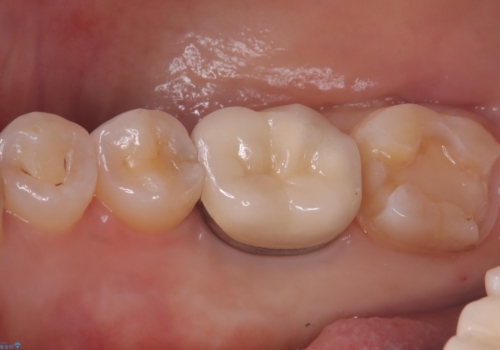

クリーニングにいらした患者さんで、右下7番目の歯の奥側の面や手前の歯との間にう蝕があり、噛む面にも蝕処置によるレジン材料が詰まっていたことから、う蝕も古い材料も全て除去しセラミックインレーでのやり替えとなりました。

右下7近遠心にカリエスを認め、咬合面のCR修復も劣化していたので、カリエスと古い材料を全て除去し新しくCR裏層した後、セラミックインレーをセットしています。セット時はラバーダム防湿を行っています。